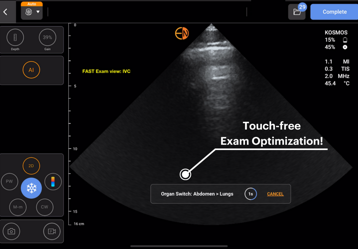

Kosmos AI

AI Fast

Identifikimi i saktë dhe në kohë reale i katërkëndëshave dhe strukturave anatomike kryesore të ekzaminimit FAST.